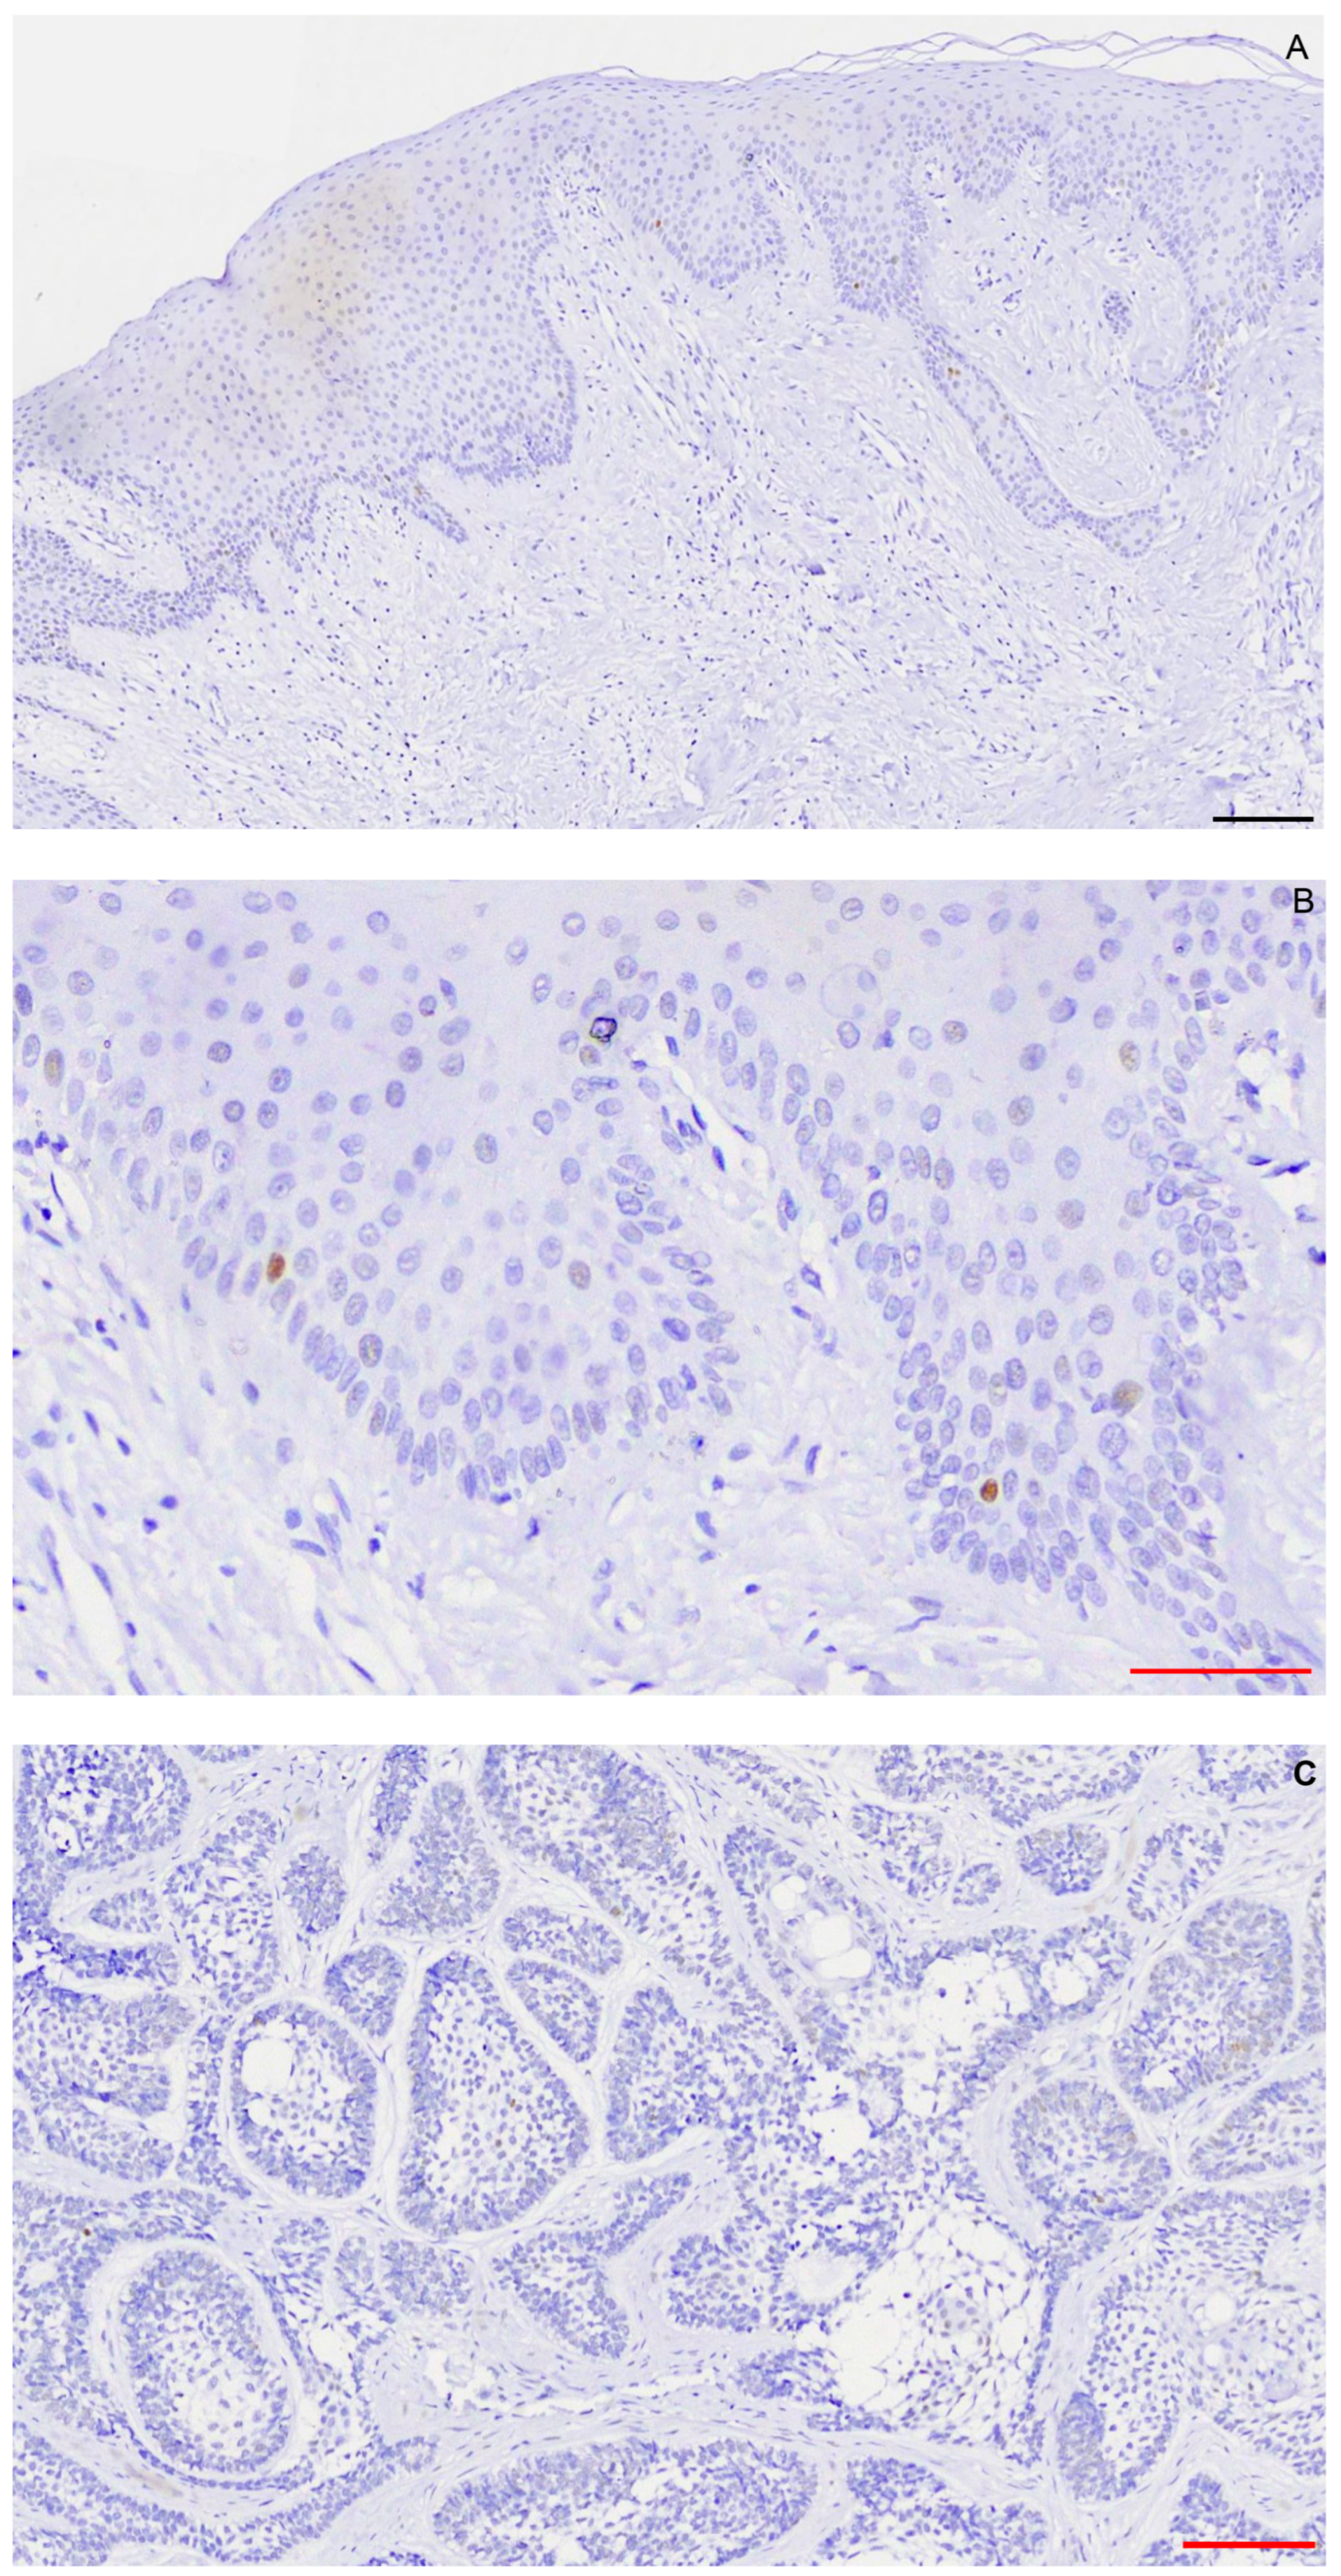

2.1. Immunohistochemistry

4.1. Immunohistochemistry